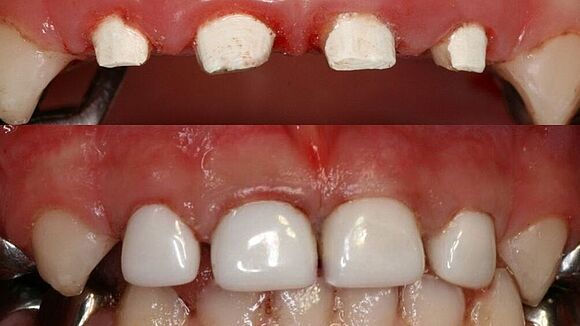

Dieses Milchgebiss wurde fachgerecht saniert. Die Karies ist verschwunden. Die Milchzähne werden erhalten, bis sie von den bleibenden Zähnen ersetzt werden. Dafür wurden auch Milchzahnkronen eingesetzt. Jetzt sind beste Bedingungen für eine effiziente Prophylaxe gegeben.